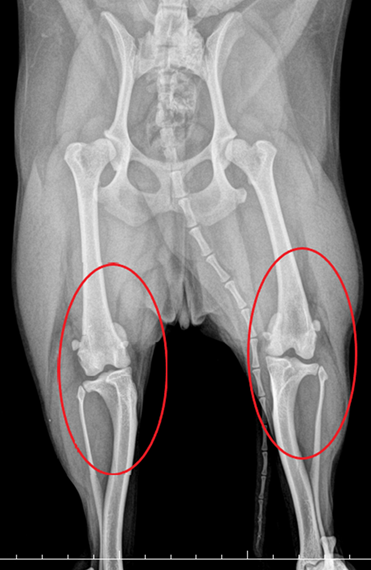

강아지 슬개골 탈구 수술 후기 (슬개골탈구 수술비용 수술과정 포함)

우리 몽실이 슬개골 탈구 수술 경험을 공유하려고 합니다. 많은 분들이 강아지 슬개골 탈구에 대해 걱정하...